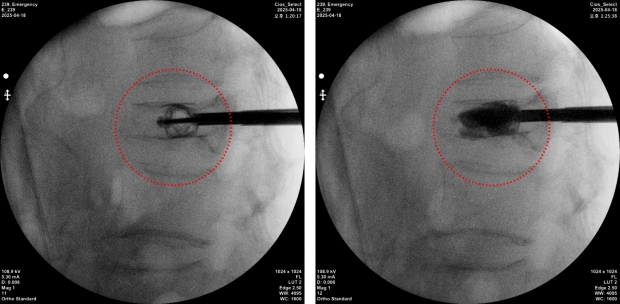

스파인잭 티타늄 임플란트를 삽입해 척추압박골절 환자의 척추체를 정상에 복원한 모습, (국제바로병원제공)

척추압박골절은 x-ray와 단층화 촬영(CT)으로 먼저 진단을 하게 되는데, 척추관 협착증까지 동반한 경우 추가 MRI 정밀검사가 필요할 수도 있다. 이때 풍선성형술과 같이 한번에 풍선을 주입해 확장한 후 시멘트를 삽입하는 기존수술법보다 티타늄 임플란트를 통해서 단계적으로 의료진의 술기에 따라 척추체 확장이 가능해 환자의 해부학적인 원래의 척추뼈 모양대로 복원이 가능하고, 재골절율을 감소시킨다고 보고 되고 있다.

국제바로병원의 첫 수술을 성공적으로 마친 70대 초반 여성환자의 경우에도 지난 1월 빙판에 미끄러져 넘어진 후 척추압박골절이 발생되었고 보존적 치료에도 통증이 지속되어 내원하였다. 신의료기술인 스파인잭을 이용한 척추체 보강술을 시행하였으며, 척추체 높이가 정상에 맞게 복원되고 유지되므로 재발된 통증이 없어지고, 척추변형이 심한 경우 척추 후만증으로 무너져 상태가 추가로 악화되는 것을 예방 할 수 있게 되었다.